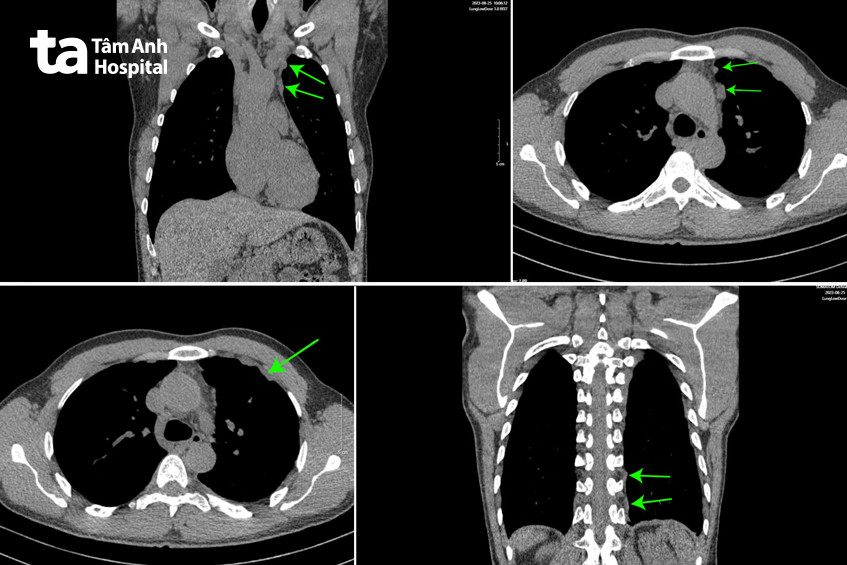

Bác sĩ Bệnh viện Đa khoa Tâm Anh Hà Nội đánh giá tình trạng bệnh lý phức tạp của ông Phong, đau ngực kéo dài hơn một năm, không xác định rõ nguyên nhân và quyết định hội chẩn đa khoa hô hấp, ung bướu, giải phẫu bệnh và ngoại lồng ngực. Người bệnh được chỉ định thực hiện chụp CT phổi liều thấp để tầm soát ung thư phổi. Kết quả cho thấy thể tích 2 phổi bình thường, không nhìn thấy tổ chức tổn thương nhưng màng phổi bên trái xuất hiện nhiều nốt sần theo mảng, nghi ngờ ung thư.

PGS.TS.BS Chu Thị Hạnh, Trưởng khoa Hô hấp, Bệnh viện Đa khoa Tâm Anh Hà Nội, cho biết thông thường ung thư phổi gây ra triệu chứng như ho, khó thở, khàn giọng, ho máu, tổn thương tại nhu mô phổi… Nhưng ông Phong không xuất hiện các triệu chứng này. Phim chụp cắt lớp vi tính phổi biểu hiện nốt sần ở màng phổi, dày màng phổi nhưng hình ảnh trên phim chụp mờ nhạt, dễ bị bỏ qua khiến tình trạng đau ngực kéo dài hơn một năm không chẩn đoán được nguyên nhân dù ông Phong đã đi khám nhiều nơi. Hội chẩn đa chuyên khoa.